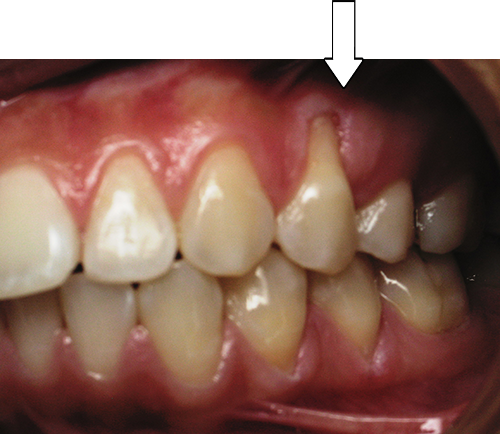

After Series of Teeth Extractions, Upper Left Canine Unerupted.

Ready to Start Ortho Treatment